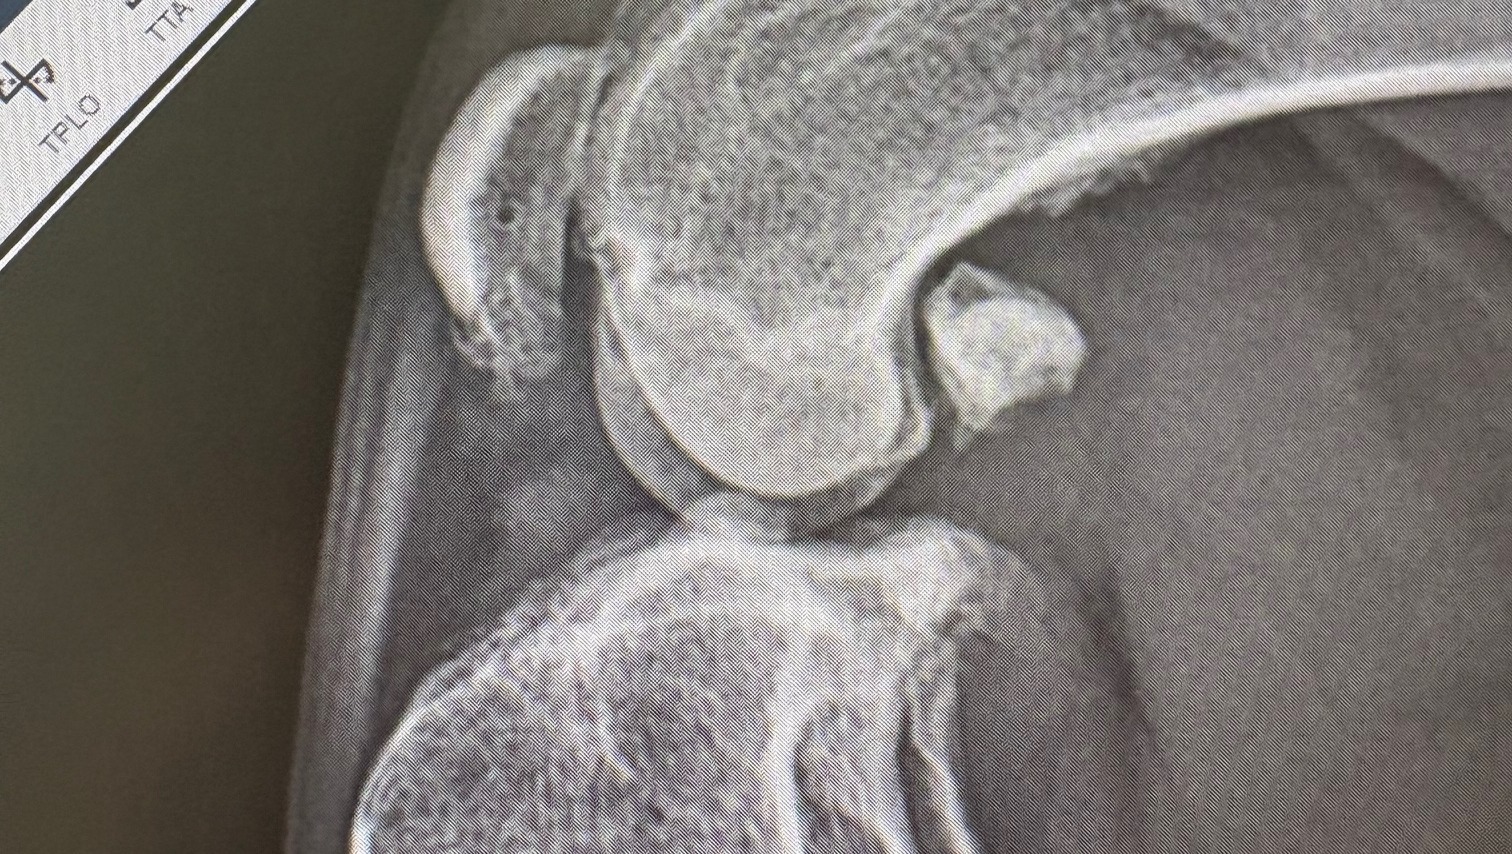

In August 2024, my sweet Loo tore the ACL in her right back leg - a painful and debilitating injury for dogs. The ACL (anterior cruciate ligament) keeps the knee stable, and when it tears, every step is a struggle. She needed an extensive surgery that cost around $7,000. It was a tough hit financially, but there was never a question - we had to help her. With the help of my amazing parents, who I’m so grateful for, we made it happen.

For a while, she did great and was on the road to recovery. But just a few months later, she started limping again - this time on her other back leg. Our vet suspected the same injury, but at the time, X-rays didn’t show a full tear. We’ve done everything we can over the past year to keep her comfortable and happy.

Now, almost a year later, her pain has come back, this time worse. New radiographs have confirmed what we were afraid of - her left ACL is torn, and she needs surgery as soon as possible. Watching her struggle to simply walk breaks my heart. She’s only seven and still has so many adventures ahead of her - giving up is not an option.